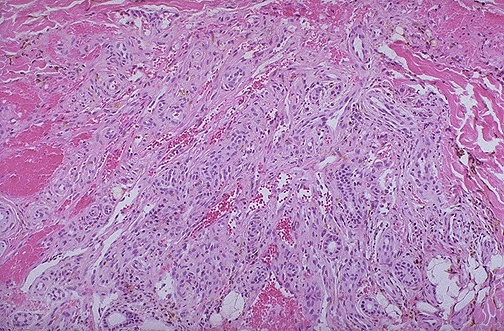

- Гистологическое исследование. Проводится для обнаружения новых сосудов (ангиоматоз) и фибробластов;